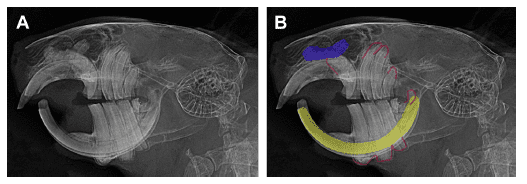

Images CT du plan sagittal de l’arcade dentaire maxillaire reconstruite en modèle 3D, vue médio-latérale médiolatérale (A), et reconstruction de surface (B).Ll’allongement apical et la couronne de réserve de la quatrième prémolaire ont fait éruption dans la cavité nasale (A), avec un apex bombé dans l’os nasal (B). Structure irrégulière suggérant des changements dysplasiques de la dent structures. Les images reconstruites sont visualisées en utilisant le logiciel de rendu de volume Drishti. (Vladimir Jekl et Tomas Zikmund).

Radiographie latérale du crâne d’un degu qui a été présenté avec une dyspnée. Les radiographies montrent une grave élongation coronale et des déformations apicales des prémolaires/molaires avec formation d’une pointe de la couronne clinique d’une prémolaire mandibulaire (flèche). Les apices malades de toutes les dents de la joue sont clairement visibles (lignes rouges). L’anomalie radiographique apicale d’une prémolaire maxillaire indique un changement dysplasique (pseudo-dontome, bleu). L’examen histopathologique a confirmé la présence d’un pseudo-dontome de la prémolaire et d’un élodontome dans la cavité nasale. (Vladimir Jekl)